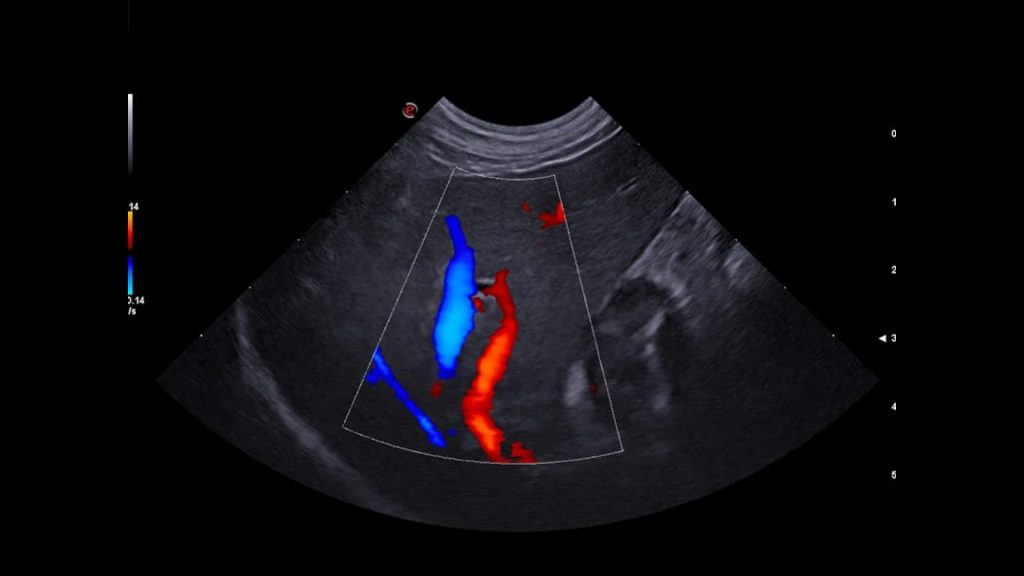

Kedi ve köpeklerde, portal sistem, caudal vena cava, aorta ve iliak damarların trombus ve embolileri ultrasonografi ile tespit edilebilir. Aortik ve iliak tromboembolizm, kedilerde kardiyomiyopatiyle birlikte ortaya çıkan önemli bir komplikasyondur. Köpeklerde Aortik ve iliak tromboembolizm, genellikle hiperkoagülasyon durumlarıyla birlikte, kardiyak hastalık ve neoplazmalarla ilişkili bir hastalık olarak ortaya çıkar. Kedi ve köpeklerde, portosistemik şantlar dışında, abdominal vasküler malformasyonlarla nadiren karşılaşılır.

Karaciğer ultrasonografisinde, hepatik parankim (karaciğer dokusu), büyük hepatik ve portal damarlar, bitişiğinde caudal vena cava ve safra kesesi ve bilier sistem incelenir. Radyografiden farklı olarak ultrasonografi, hedef yapıların çeşitli düzlemlerden görüntülenmesine olanak sağlar. Karaciğerin ultrasonografik muayenesi sırasında hekimin tercihine göre hasta sağ yan, sol yan veya sırt üstü pozisyonlarında yatabilir. Daha iyi görüntü alınabilmesi için karın bölgesi göğüs bölgesine kadar tıraşlanıp temizlenmelidir. Görüntü kalitesini hastanın vücut yapısı, karaciğerin boyutu ve gastrointestinal içerik etkileyebilir. Mide içeriğindeki gaz iyi bir karaciğer görüntülemesinin önündeki en önemli engeldir. Bu sebeple hastanın aç olarak muayene getirilmesi tercih edilir. Karaciğer ultrasonografisine ihtiyaç duyulan durumlar, karaciğer hastalıklarıyla ilişkili klinik belirtiler (kusma, ishal, abdomende genişleme, abdomenin elle muayenesinde karaciğer boyutunun arttığının farkedilmesi vs.), laboratuvar analizlerinde biyokimyasal değişiklikler (ALT, ALP, AST, NH3, GGT, BİLİRUBİN, TOTAL PROTEİN, ALBUMIN), ikterus (sarılık), hepatomegali, asites, akut abdomen veya abdominal kitle şüphesi, metastatik kitle şüphesi, hepatik enseflaopati, immun sistem hastalıklarını içermektedir. Hepatik arterleri ve intrahepatik dallarını görüntülemek için Doppler muayenesi gereklidir. Doppler ultrasonografi ile hepatik arter, portal ven ve caudal vena cava incelenebilir. Konjenital veya edinsel Portasistemik Şantla (PSŞ) ilişkili klinik veya laboratuvar belirtileri olan hayvanlarda intrahepatik veya ekstrahepatik anormal damarlar da saptanabilir. Doppler görüntüleme ile aynı zamanda intrahepatik portal hipertansiyonun da tanısı konulabilmektedir.

Veteriner hekimlerimize ve sevimli dostlarımıza merkezimiz bünyesinde vermiş olduğumuz Veteriner USG hizmetimizde Esaote MyLAB X8VET Üst Düzey Renkli Doppler Ultrasonografi Cihazı ile hizmet vermekteyiz. Cihaz ile yapılan sonografik ve doppler çalışmalarında her türlü patolojilerde yüksek çözünürlükte görüntüleme imkanı sağlanmaktadır. İçerdiği yazılımlar ile tanıyı detaylandırarak teşhise götüren götürmeye yardımcı olmaktadır. Çoklu modalite aracı ile, hızlı bir tanıya ulaşmak için gerçek zamanlı ultrason görüntülemeyi çok çeşitli ikinci görüntüleme modaliteleriyle (MRI, CT, 3D Görüntüleme, Doppler) birleştirmek mümkündür.